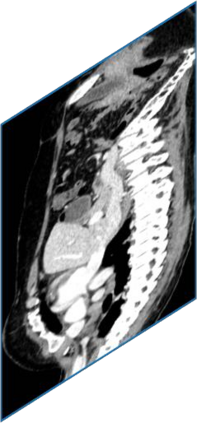

Due to the constraints of the imaging device and high cost in operation time, computer tomography (CT) scans are usually acquired with low intra-slice resolution. Improving the intra-slice resolution is beneficial to the disease diagnosis for both human experts and computer-aided systems. To this end, this paper builds a novel medical slice synthesis to increase the between-slice resolution. Considering that the ground-truth intermediate medical slices are always absent in clinical practice, we introduce the incremental cross-view mutual distillation strategy to accomplish this task in the self-supervised learning manner. Specifically, we model this problem from three different views: slice-wise interpolation from axial view and pixel-wise interpolation from coronal and sagittal views. Under this circumstance, the models learned from different views can distill valuable knowledge to guide the learning processes of each other. We can repeat this process to make the models synthesize intermediate slice data with increasing inter-slice resolution. To demonstrate the effectiveness of the proposed approach, we conduct comprehensive experiments on a large-scale CT dataset. Quantitative and qualitative comparison results show that our method outperforms state-of-the-art algorithms by clear margins.